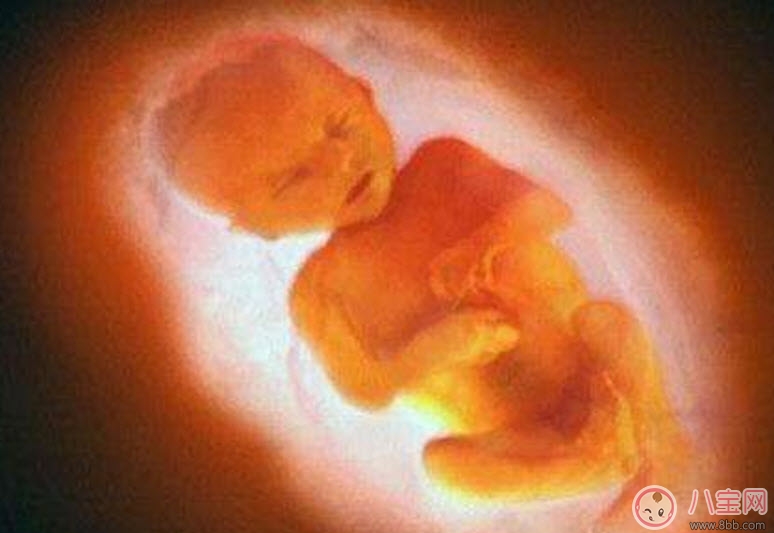

四维彩超的作用1、确定预产期:一般在孕妇20周左右做四维彩超检查 , 因为这个时候的彩超能比较准确地推算预产期 。

2、查看胎儿的活动:可以检查到胎儿在宫内是否缺氧 , 肢体运动、胎儿的吞咽动作等 , 能够很好的看到胎儿在母体内的活动状况 。

3、监测胎儿生长发育:医生解释 , 检测胎儿发育是根据测量胎儿的数值来判断 , 如果低于第10百分位 , 或高于第90百分位的话 , 胎儿就是不正常的了 。

4、胎儿是否畸形:彩超检查时发现胎儿畸形的一个重要的手段 。一旦发现胎儿畸形 , 就可以及时终止妊娠 , 通常孕妇在妊娠22-26周做彩超可以筛查胎儿是否畸形 , 因为这个时段的胎儿各个器官都已经发育成型形 , 比较容易看出有没有畸形 。所以做彩超检查十分重要 。

5、测量羊水量:彩超可以比较准确地测量羊水量 。母体羊水量的多少对胎儿的发育非常的重要 , 因为羊水太多或者太少都会导致胎儿畸形 。在彩超中也可以清楚地了解胎盘的位置是否正常 , 胎盘是否有血管瘤的存在 , 是否成熟等 , 可以明确地诊断出前置胎盘 , 胎盘早剥等危险情况的存在 。